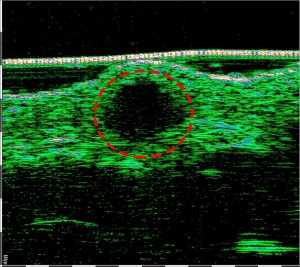

Επιπλοκή μετά από έγχυση filler. Κοκκίωμα προκαλούμενο από ξένο προς το δέρμα σώμα.

-Επιπλοκή, κοκκίωμα μετά από έγχυση Filler